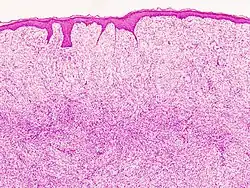

Histopathological image of dermatofibrosarcoma protuberans. Local recurrence long after the first excision. H&E stain | |